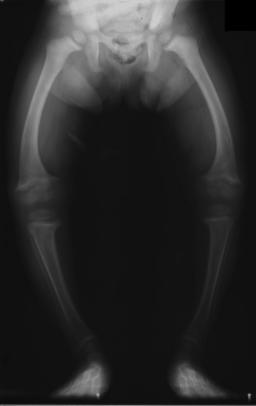

- 我們並非第一個到達歐洲的人屬動物。早在25萬年前就有另一個叫尼安德塔人的人種住在歐洲了,尼安德塔人四支短小,肌肉發達,工具精良,頭腦優秀,是當時最頂尖的獵人,但他們最後還是被智人所滅,從此智人便稱霸了歐洲。